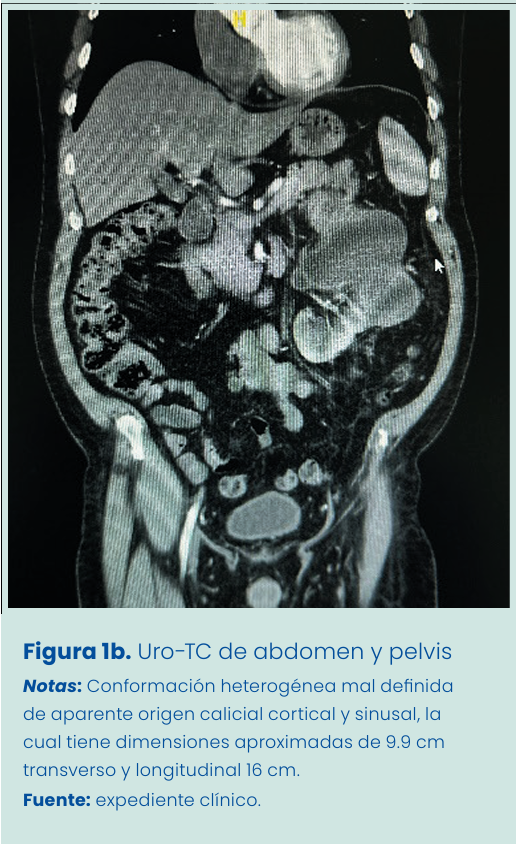

Resonancia magnética nuclear (RMN) de abdomen y pelvis evidencia riñón izquierdo aumentado de tamaño de aspecto dismórfico, heterogéneo, con áreas de importante adelgazamiento cortical hacia su polo inferior y tercio medio, con dilatación focal y deformidad de los cálices, los cuales condicionan dilatación del sistema pielocalicial. Imagen de baja intensidad en el trayecto de la pelvis, que oblitera de forma parcial, adoptando aspecto quístico, con septos y discreto componente hiperproteico asociados a engrosamiento mural a nivel de grupos caliciales y trayecto de la pelvis superior, que sugiere contexto crónico agudizado. Polo inferior del riñón izquierdo se valora parcialmente, identificándose grosor cortical con pelvis independiente, la cual se valora excretando, sugiriendo sistema pielocalicial bífido. Urografía por tomografía (URO-TC) (Figura 1a) revela riñón izquierdo aumentado de tamaño, con formación heterogénea mal definida de aparente origen calicial cortical y sinusal, la cual tiene dimensiones aproximadas de 9.9 cm transverso y longitudinal 16 cm, sugiriendo dilatación focal de los cálices en el polo superior, tercio medio distal del riñón, presentando heterogenicidad de su contenido. Borde con contenido hiperproteico/hemorrágico sin descartarse la posibilidad de componente tisular (Figura 1b).